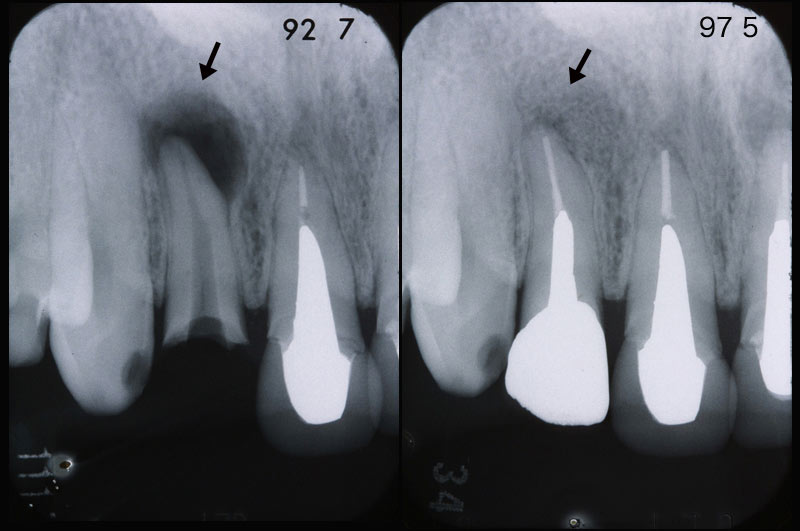

歯科医院でレントゲンを撮って説明を受けたことがあると思います。歯科のレントゲンフィルムは小さくてよくわからなかったという方が多いのではないでしょうか。レントゲンフィルムの種類や撮影法、現像法には多くの種類がありそれによって画像の鮮明度には差がでてきます。須貝歯科医院ではレントゲン診断にこだわり鮮明な画像が得られるようにシステムを整えています。また撮影されたレントゲンはパソコンのモニター上に拡大し、素人の患者さんが見てもわかるようしています。

上のレントゲンでは根の先端に大きな病巣があるのがわかります。右側が治療後ですが病巣が消えています。歯を入れるだけでなくレントゲンで骨の状態の改善が確認できなければ本当に治ったとは言えません。